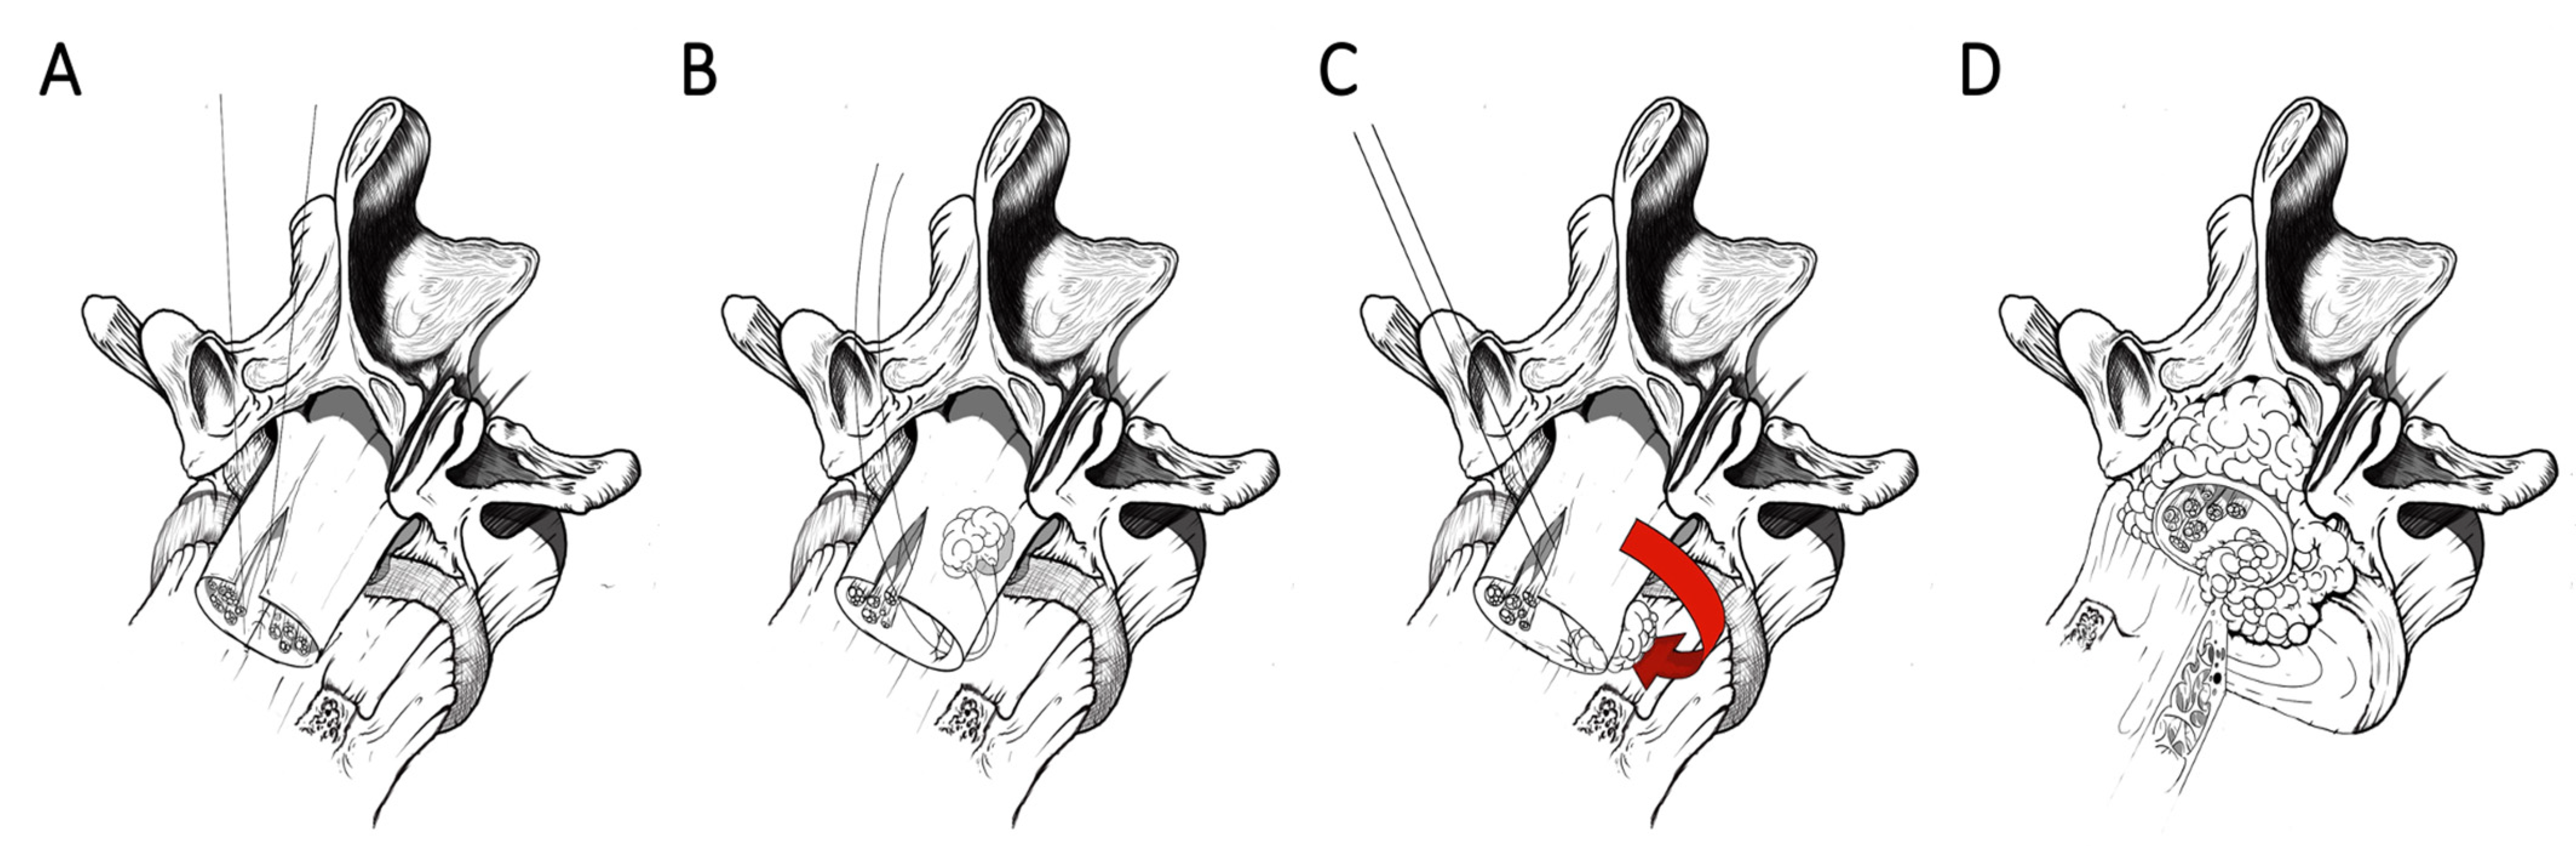

3. Coating Techniques

3.1. Dural Coating

3.2. Dural Coating Straddling Nerve Roots

3.3. Dural Coating with Sutured Fat Graft